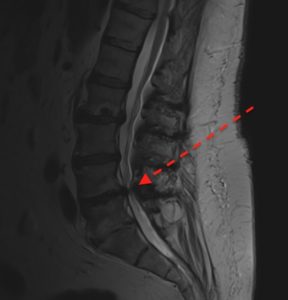

Estenosis es un término médico que puede traducirse por estrechez. La médula se ubica en un canal vertebral configurado por vértebras, ligamentos, discos y articulaciones. Si este canal se estrechara, por ejemplo, entre las vértebras L4-L5 se denominaría estenosis de canal segmentaria L4-L5 o simplemente estenosis L4-L5. Nos referimos a canal estrecho congénito cuando todo el canal tiene calibres reducidos en relación a la media. Puede aparecer una estenosis segmentaria sobre un canal estrecho congénito. La estenosis de canal lumbar es una de las patologías más comunes en cirugía de columna.

El diagnóstico es clínico y radiológico. La resonancia es esencial. Las radiografías aportan información técnica de la carga en estática, balance y comportamiento de la columna en flexión y extensión. El Tac lumbar se solicita cuando se requiere información técnica para planificación quirúrgica. Los pacientes con déficit de irrigación en piernas suelen presentar sintomatología muy similar aunque en este caso toleran mejor estar de pie que caminar.